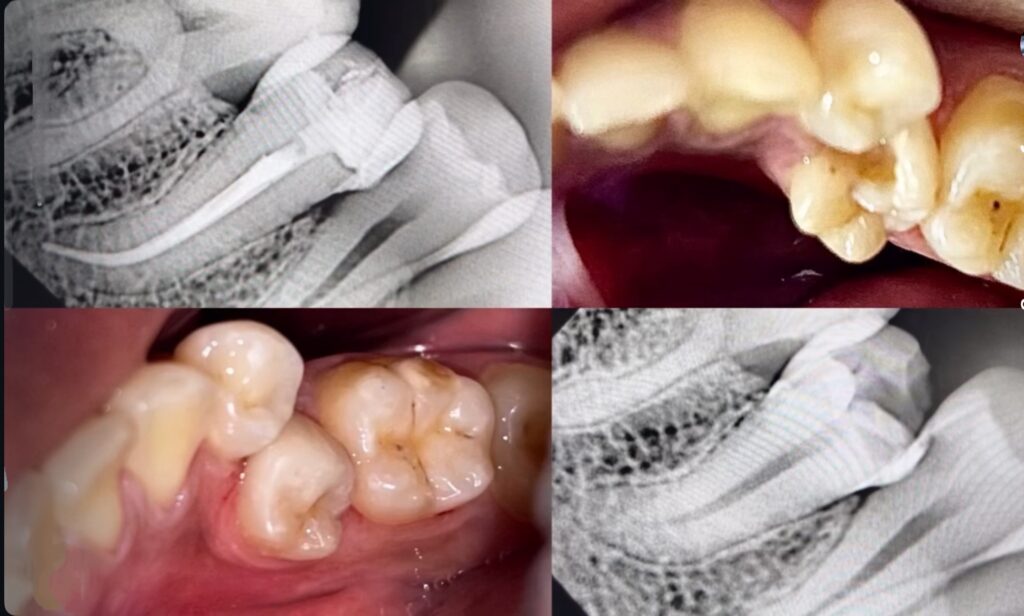

Root canal therapy (RCT) is a dental procedure used to treat infected or damaged tooth pulp.

The tooth pulp is the innermost layer of the tooth and it can be damaged due to extensive decay or trauma.

Treating the pulp for RCT preserves the remaining tooth structure and prevents it from further damage or extraction.

Procedure

Following X-ray and diagnosis, the tooth is numbed with local anesthesia

Drilling of tooth to clean the decay and the infected pulp

Disinfection ,filling and sealing of the pulp canals.

To restore function, tooth is filled with a filling and may require a crown.